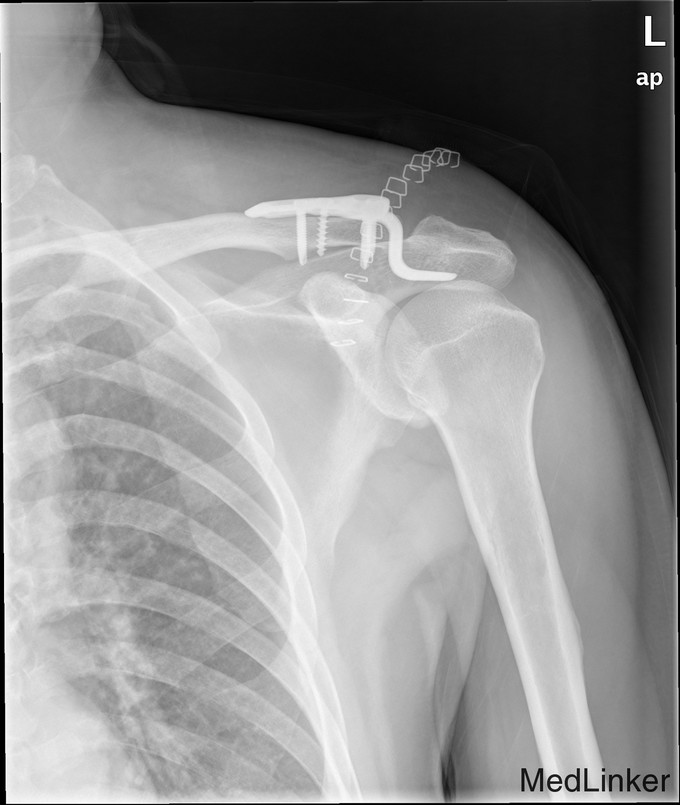

完善术前检查和准备后,行左肩锁关节脱位切开复位内固定术,术顺,术后安返病房,内固定使用锁骨钩。

随访示内固定在位,复位位置可。